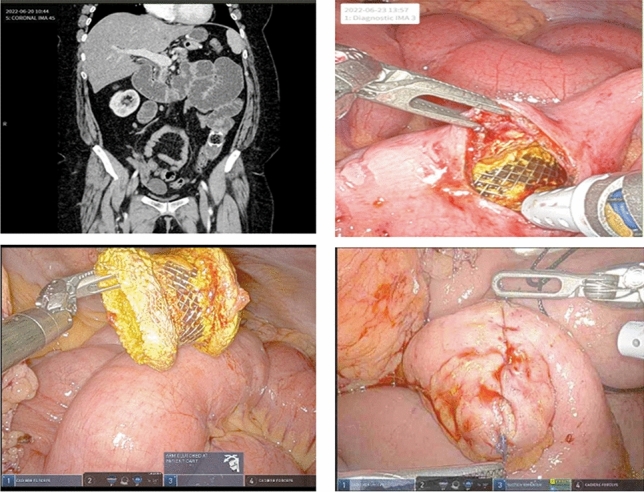

“Sandwich” Approach to Complex Flank Hernia Repair: A Case Series of 8 patients

Jason Aubrey, MD1; Aryana Sharrak, MD1; Anne Opalikhin, BS2; Amy Banks-Venegoni, MD3; 1Department of General Surgery, Spectrum Health/Michigan State University; 2Michigan State University College of Human Medicine; 3Department of General Surgery, Spectrum Health Blodgett Hospital

Objective: Flank hernias are rare and challenging to repair given their unique anatomic locations. There are limited prospective studies describing repair techniques. Obtaining overlap of mesh during repair is difficult due to the lack of strong fascial layers laterally. Open repair of flank and lumbar hernias can have complication rates of up to 40% and recurrence rates of 0–15.9%. Laparoscopic repair improves complications and recurrence (0–37% and 0–2.9%, respectively) with variable outcomes.

Our case series describes a novel technique of open onlay combined with a robotic underlay mesh. The study provides a technical description of a two-layered mesh resulting in a “sandwich” and assess surgical outcomes for a new surgical approach for flank hernias.

Methods: Our study is a retrospective chart review for repair of complex flank hernias with open onlay and robotic underlay by a single surgeon from November 2017 to September 2022. IRB approval was obtained through Spectrum Health.

Results: The cohort contained eight patients that included six males (75%) and two females (25%) with a mean age at repair of 64 years old (R: 42–88) and mean BMI was 29.7 (R: 23.4–36.1, SD: 4.2). Seven hernias (87.5%) were the result of prior surgeries, three AAA repairs, three nephrectomies, and one spinal surgery. One hernia (12.5%) was the result of a motor vehicle collision. Five (62.5%) were reducible. Mean hernia defect width was 8.6 cm (R: 4–15, SD: 3.93). Mean hernia defect length was 5.9 cm (R: 3–10, SD: 2.1). Mean operative time was 248 min (R: 169–428, SD 87.0). Mean length of stay was 1.75 days (R: 0–5, SD: 1.83). Five (62.5%) patients were able to be discharged without narcotics. One (12.5%) patient developed a hematoma and one (12.5%) a seroma; both managed conservatively and without clinical sequela. One patient required re-admission in the 30-day post-operative period for pain control. There have been zero hernia recurrences confirmed by CT scan at a mean follow-up of 20.75 months (R: 1–56, SD: 19.2).

Conclusion: This study outlines a novel approach to complex flank hernia repair with an open onlay and robotic underlay mesh placement for a “sandwich” technique. With minimal postoperative complications and no recurrences, the sandwich technique might be the better approach to a more durable flank hernia repair. Further prospective trials need to be performed to elucidate a gold standard technique.